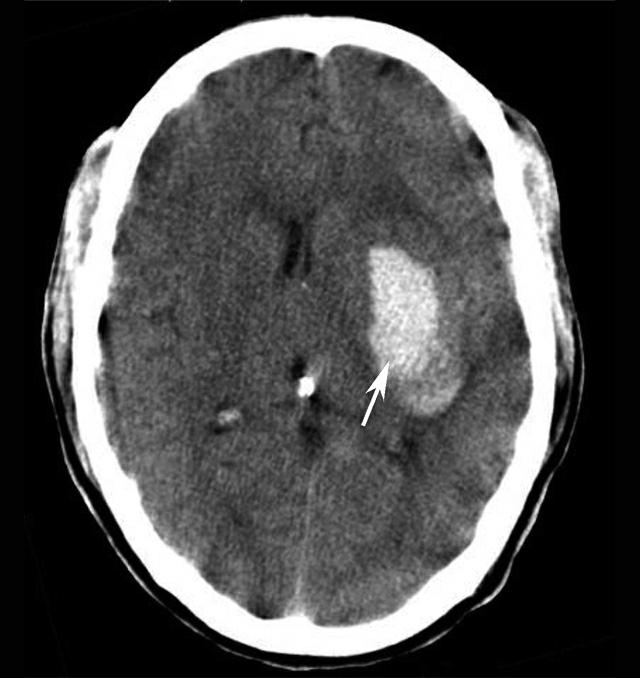

图1-2-90 左侧基底节区血肿

左侧基底节区示一团块状高密度病变(箭),CT值约为80HU,周边示轻度低密度水肿影。左侧侧脑室受压,中线结构右移